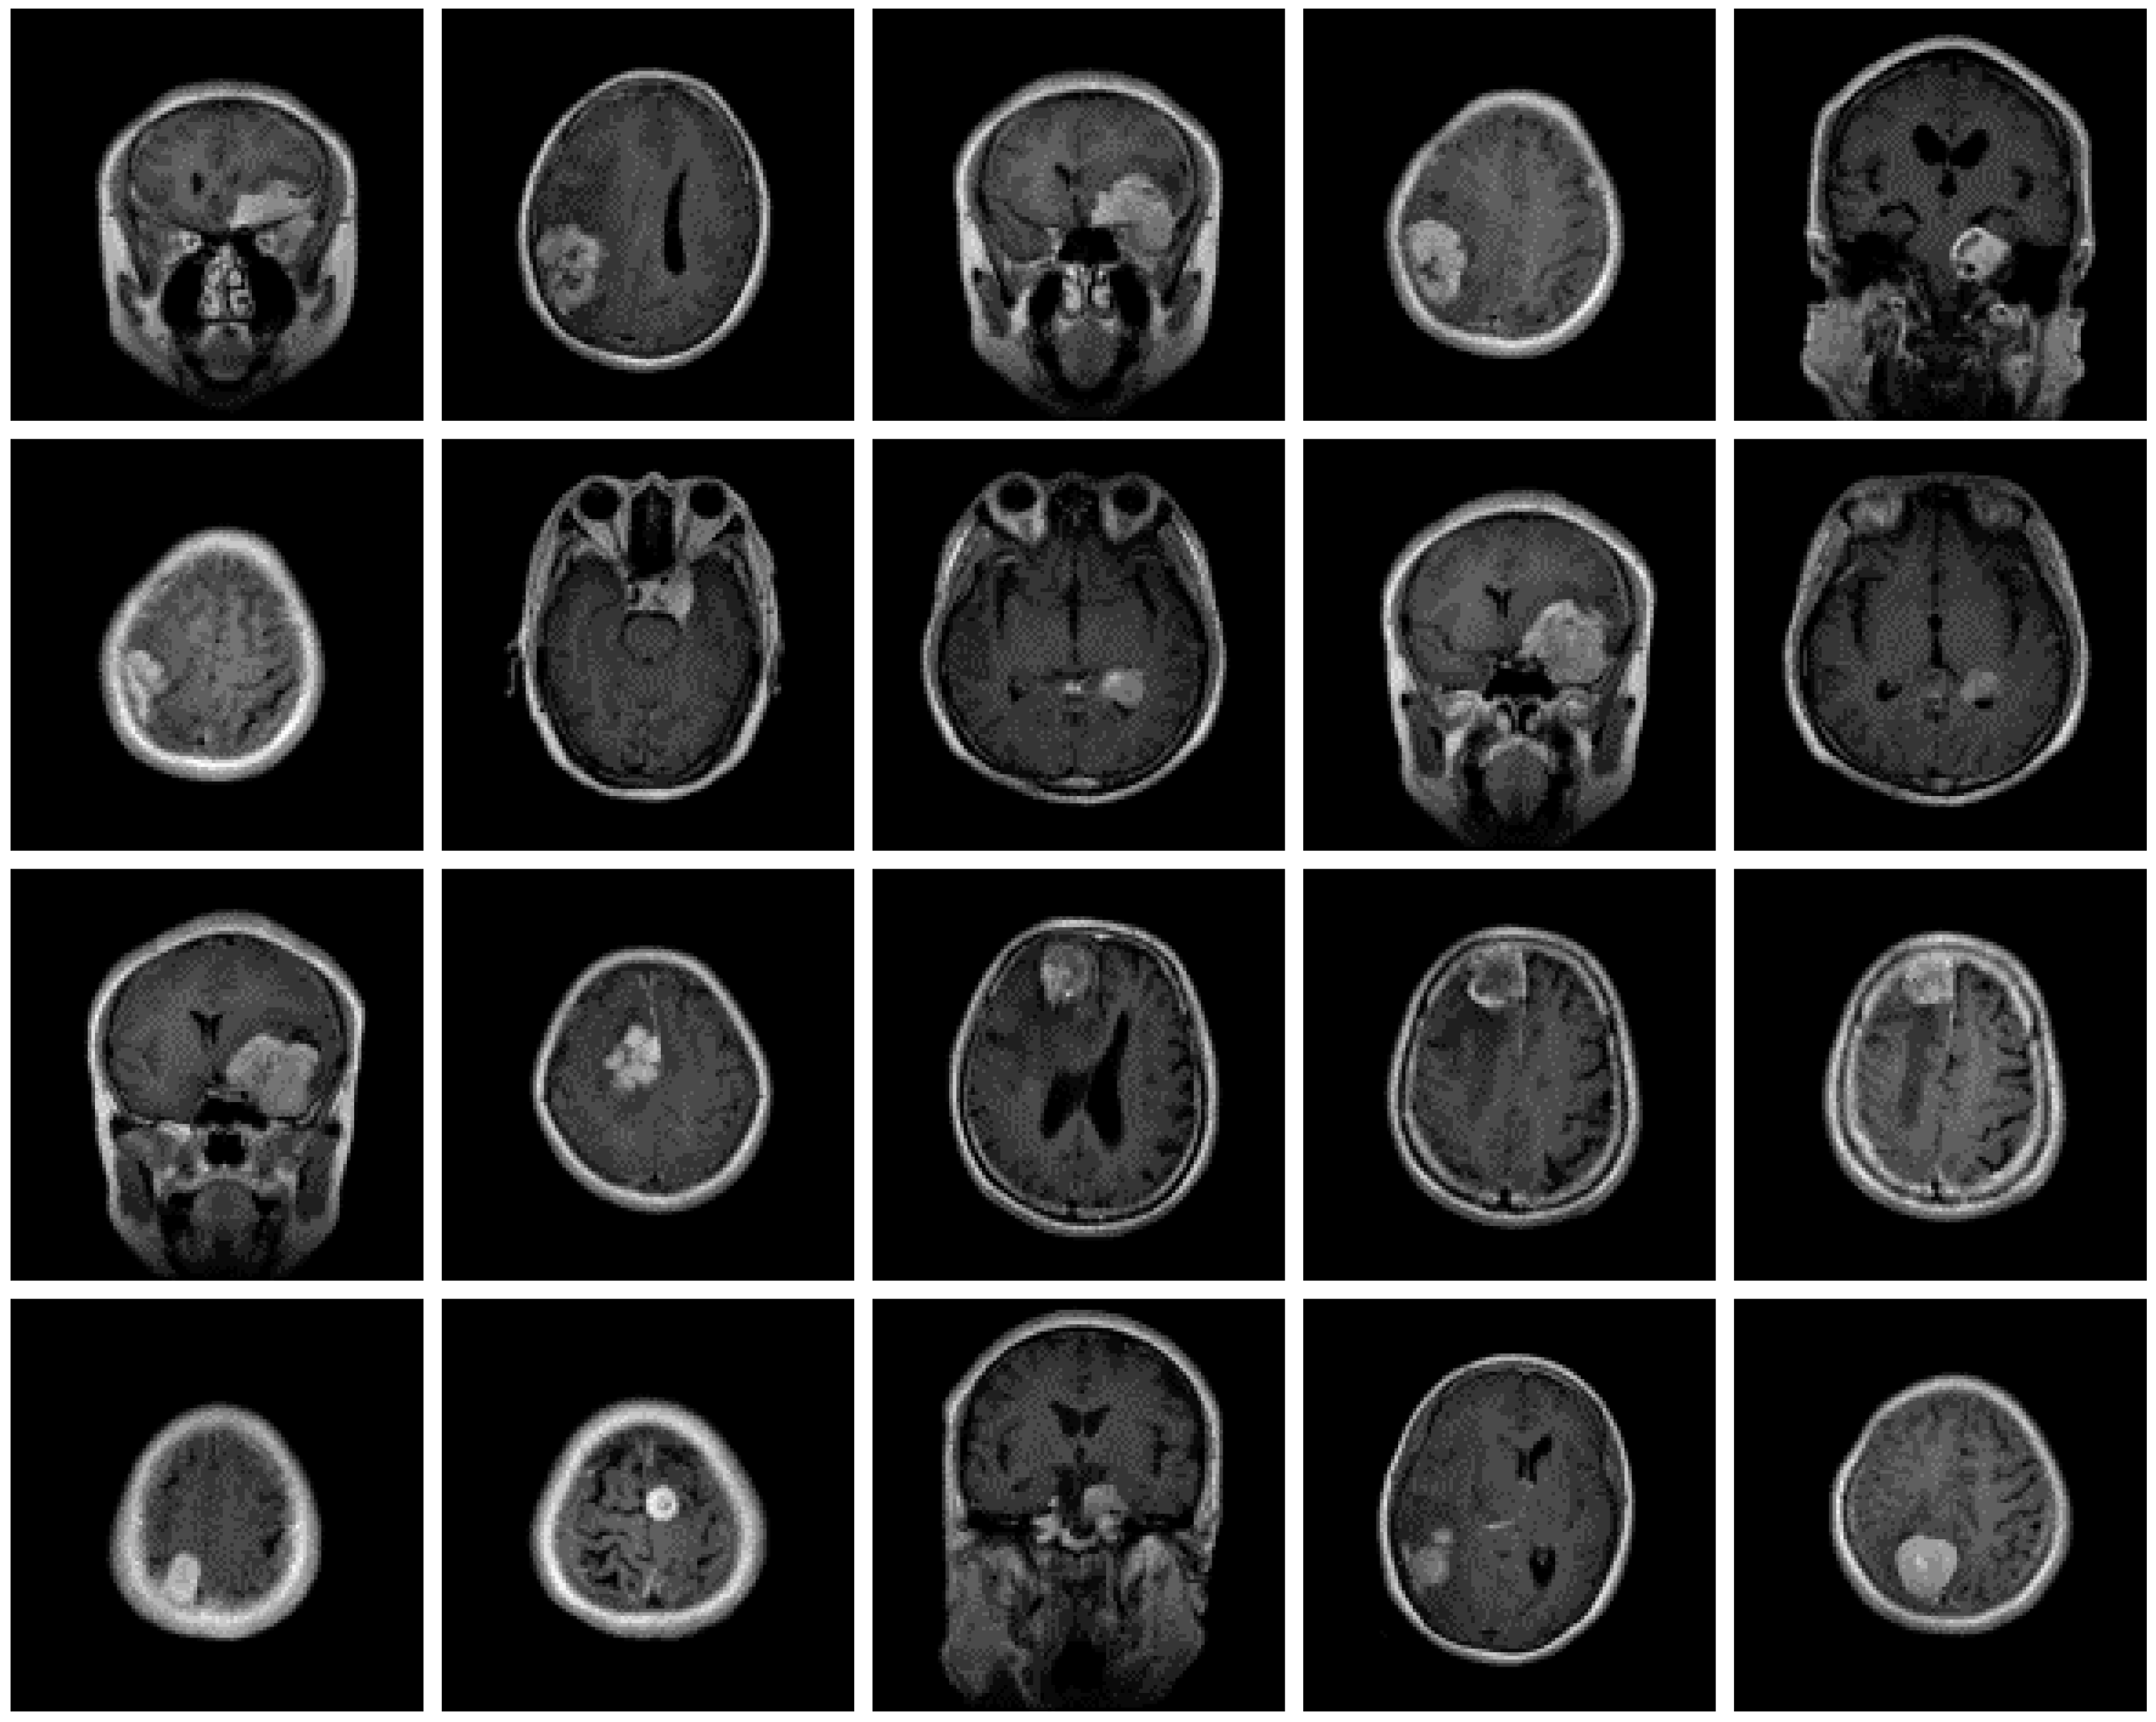

The dataset used for this current work is compiled from three other datasets: Figshare, SARTAJ, and Br35h. This composite dataset contains 2880 T1- weighted contrast-enhanced MRI brain images [26]. Gadolinium was used as contrast agent in these images. The target dataset has 829 images for glioma tumor, 825 images for meningioma tumor, 830 images for pituitary tumor and 396 images for no tumor cases. The images of the target dataset have a resolution of 512 × 512 × 3 with 24 bits color depth. Figure 1, Figure 2, Figure 3 and Figure 4 show some examples for each possible class: no tumor, glioma, meningioma, and pituitary tumor, respectively. The target dataset is split with 70% used for training and the remaining 30% kept aside for estimating the validation accuracy.

Figure 4.

Examples of MRI scans of pituitary tumors.